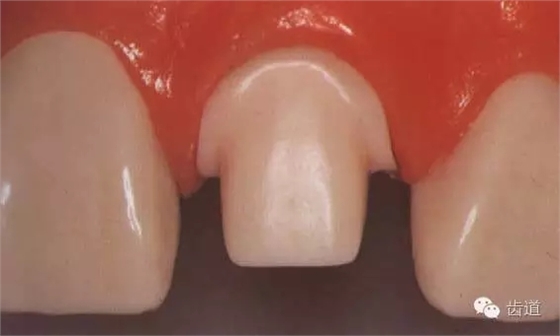

1、檢查牙體預(yù)備的切割量

保證去除倒凹

肩臺(tái)的寬度

不同合位下的修復(fù)間隙

2、用磨光鉆修光牙面